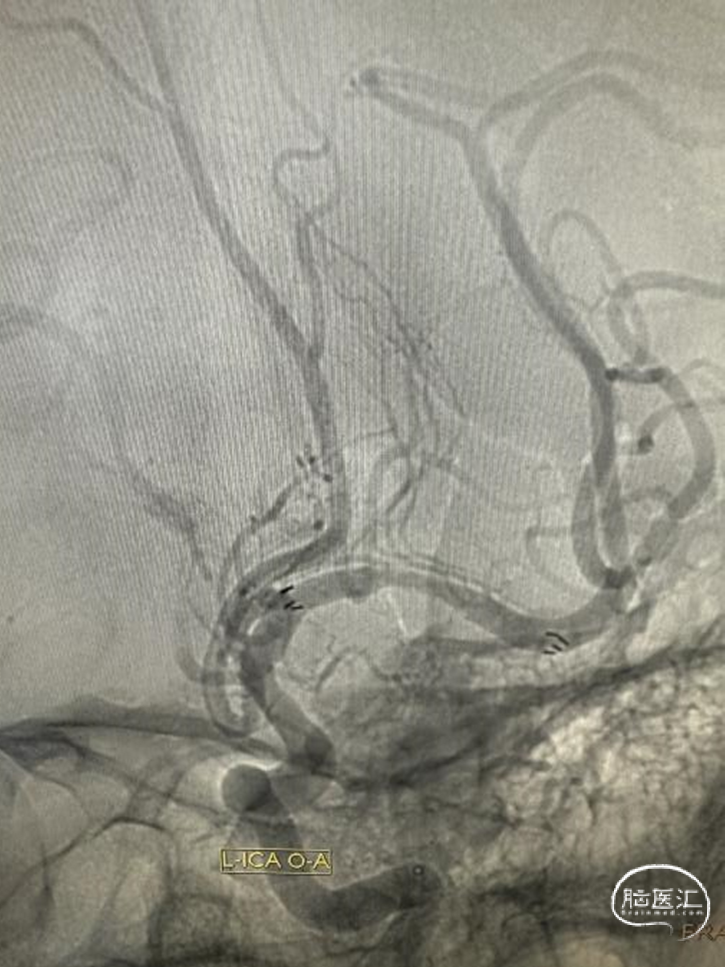

DSA

左侧大脑中动脉重度狭窄,近端:1.78mm,远端:2.18mm,最窄:0.25mm,长度:14.70mm,狭窄率约:89%。

Fastunnel®输送型球囊扩张导管 2.5mm*10mm沿微导丝输送到位,充盈球囊扩张狭窄病变。

扩张后即刻造影。